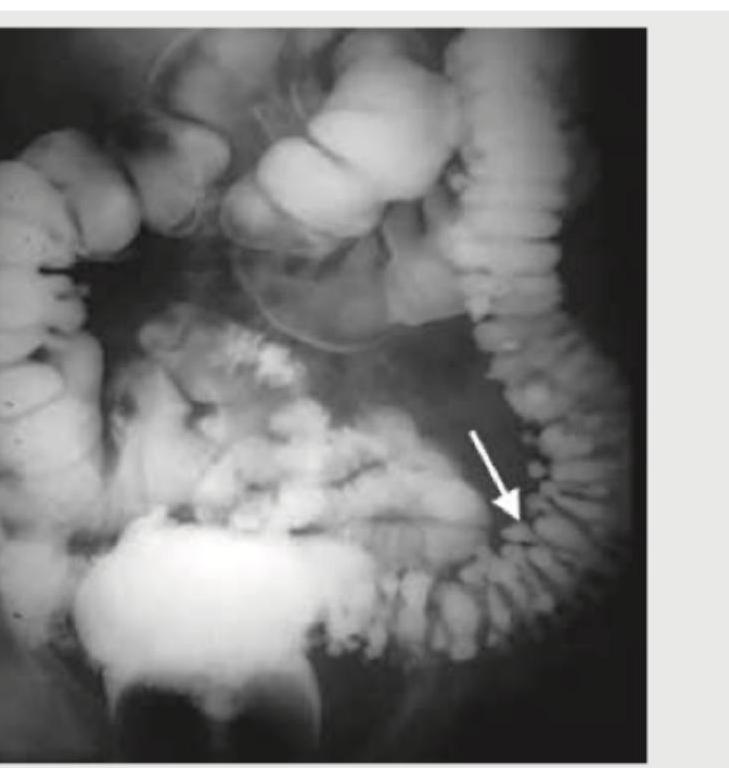

Question 6: All of the following statements regarding this image are true except:

- A. Defect occurs usually between tenia coli and the blood vessel entering colonic wall

- B. They are a result of tractional force

- C. Most common site for this defect is sigmoid colon

- D. High fiber diet will reduce the incidence of this defect (Correct Answer)

Explanation: **_High fiber diet will reduce the incidence of this defect_** - This statement is **false**. High fiber intake is generally recommended for preventing diverticular disease and not for their treatment in this case. - While fiber can reduce the incidence of diverticulosis, it does not apply to the *defect itself*, which refers to existing diverticula. *Defect occurs usually between tenia coli and the blood vessel entering colonic wall* - This statement is **true**. Diverticula commonly arise at points where **colonic blood vessels** penetrate the muscular layers, creating weak spots. - These areas are anatomically predisposed to herniation due to the passage of **vasa recta** through the muscularis propria. *They are a result of tractional force* - This statement is **true**. Diverticula are generally classified as **false diverticula** (pseudodiverticula) because they are formed by the herniation of mucosa and submucosa through defects in the muscularis. - This herniation is primarily caused by **increased intraluminal pressure** working against the weakened colonic wall, rather than external traction. *Most common site for this defect is sigmoid colon* - This statement is **true**. The **sigmoid colon** is the most common site for diverticular disease due to its narrow lumen and higher intraluminal pressure. - This region experiences the greatest stress during fecal transit, predisposing it to the formation of these outpouchings.